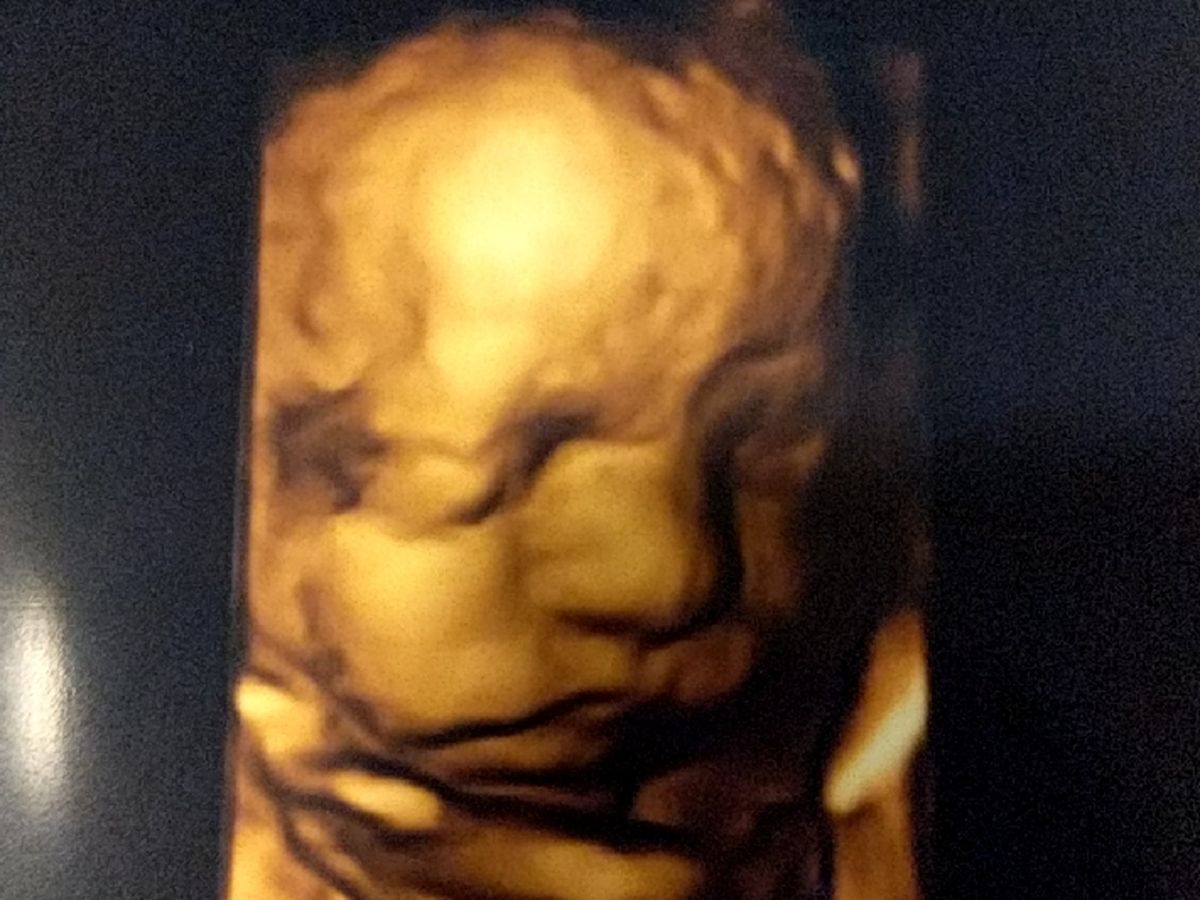

Josh and Kayla are expecting a baby boy, Noah. Noah has been diagnosed with a birth defect called congenital diaphragmatic hernia (CDH). It is a condition where there is a hernia (hole) in the diaphragm. He has stomach and intestinal parts in his chest cavity. He will be born at 38 weeks. Because of the seriousness of his condition, Kayla will have to relocate to Denver at 34 weeks and remain there until he is born and has had corrective surgery. Immediately after birth, Noah will be placed on a ventilator and a feeding tube and will be placed in the Neonatal Intensive Care Unit (NICU). Surgery will be performed to correct the hernia about 3-6 days after birth. Noah will have to be in the NICU up to 2 months following surgery. We have been told that CDH babies are some of the sickest in the NICU. When Noah is released, he will be sent home on oxygen and will need additional services such as physical therapy and speech therapy (swallowing/eating).